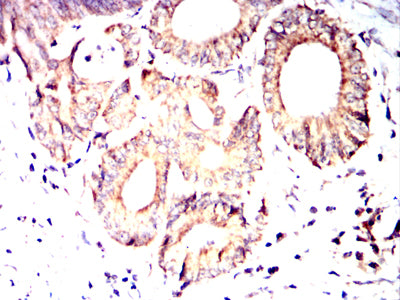

Immunohistochemical analysis of paraffin-embedded human lung cancer tissues using PDHA1 mouse mAb with DAB staining.

-

Immunohistochemical analysis of paraffin-embedded human colon cancer tissues using PDHA1 mouse mAb with DAB staining.